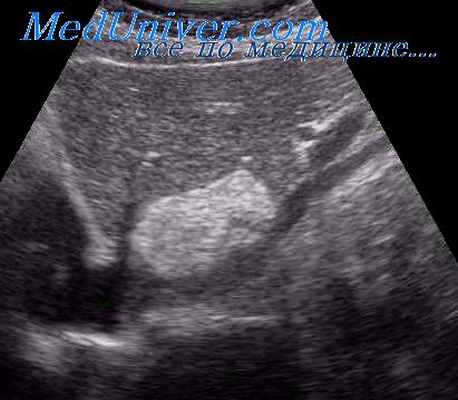

УЗИ позволяет дифференцировать солидные образования и кисты, гемангиомы и злокачественные опухоли. Метод высоко информативен для определения локализации поражения и распространенности процесса.

Эхографическое изображение новообразований печени зависит от их типа и стадии развития. Печеночноклеточный рак визуализируется в виде единичных или множественных образований неправильной формы с неоднородной эхоструктурой, окруженных тонким гипоэхогенным ободком (рис. ). Капиллярная гемангиома на эхограмме представляется в виде овальных образований с повышенной эхогенностью и ровными четкими краями. Часто визуализируются также питающие опухоль кровеносные сосуды (рис. ). Кавернозная гемангиома характеризуется неоднородной внутренней структурой и наличием эхонегативных зон различной формы и разного размера (рис. ). Метастазы визуализируются в виде единичных или множественных образований неопределенной формы с неопределенной структурой и неровными краями. При наличии некроза и распада опухоли на эхограмме выделяется участки паренхимы печени со смешанной эхогенностью.